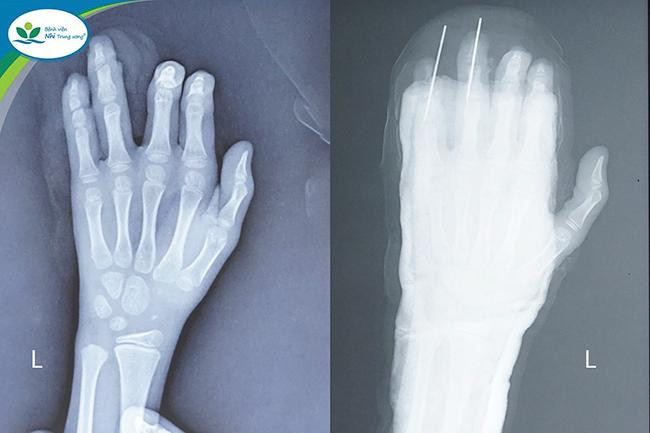

Sau khi sơ cứu, bé được chuyển đến Bệnh viện Nhi Trung ương trong đêm để tiếp tục điều trị. Tại đây, bé nhập viện trong tình trạng ngón IV-V của bàn tay trái đã bị đứt gần rời, chỉ còn phần da dập nát ở ngón tay. Ngay lập tức bé được các bác sĩ thăm khám, chụp X-quang, làm các xét nghiệm cần thiết và chỉ định phẫu thuật vi phẫu.

Thạc sĩ, bác sĩ Nguyễn Vũ Hoàng – Khoa Chỉnh hình, Bệnh viện Nhi Trung ương, người trực tiếp phẫu thuật cho bé trai cho biết, bệnh nhi gặp tổn thương rất nghiêm trọng, ngón tay IV-V bàn tay trái của trẻ đã đứt toàn bộ gân gấp, gân duỗi và một phần nguồn mạch nuôi, vết thương thấu khớp mẻ diện khớp và xương đốt ngón tay.

Để phục hồi ngón tay cho cháu bé, các bác sĩ đã tiến hành lắp ráp xương, kết hợp xương bằng đinh Kirschner, nối lại gân duỗi và gân gấp ngón tay IV-V bàn tay trái và khâu phục hồi da ngón của bé.

Ca phẫu thuật kéo gần 3 giờ đồng hồ đã cho kết quả thành công. Sau phẫu thuật các ngón tay đã hồng ấm, sức khỏe bệnh nhi tiến triển tốt.